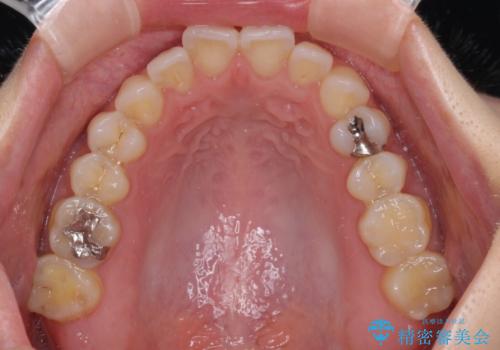

【モニター】狭い上顎歯列とオープンバイト 急速拡大装置を用いた矯正治療

- 前歯の開咬を気にして来院された患者様です。

上顎歯列が狭窄していたため、急速拡大装置により上顎骨を側方に拡大し、その後インビザラインにて矯正治療を行うこととしました。

舌の突出癖が開咬の原因であったので、改善のための舌トレーニングを行っていただきました。

舌トレーニングは後戻りにも大きく影響するため、とても重要なトレーニングです。